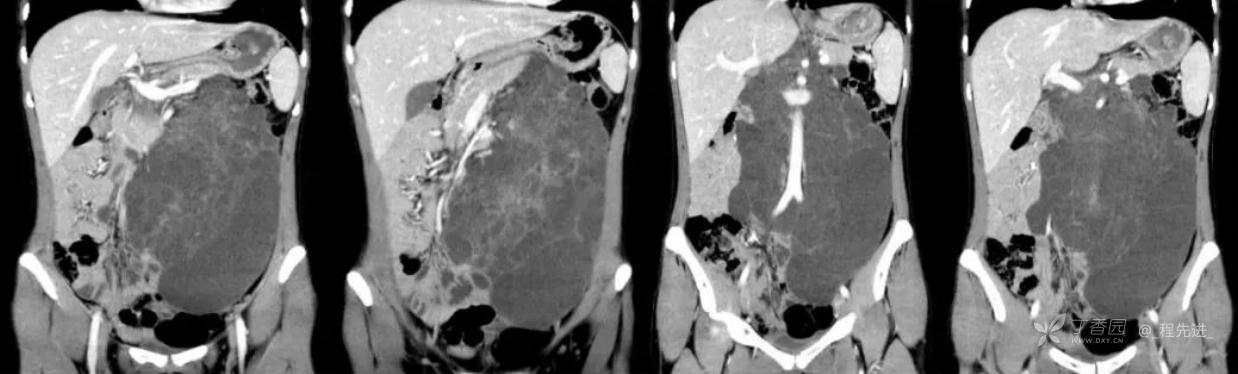

患者性别:女

患者年龄:24岁

主诉:腹痛、发热一天

现病史:一天前无明显诱因出现腹痛并发热不适,伴恶心、干呕,诊所肌注药物(具体用药不详),无缓解,无明显尿频、尿痛。

体格检查:腹肌稍紧张,右上腹部轻压痛,右肾区叩痛